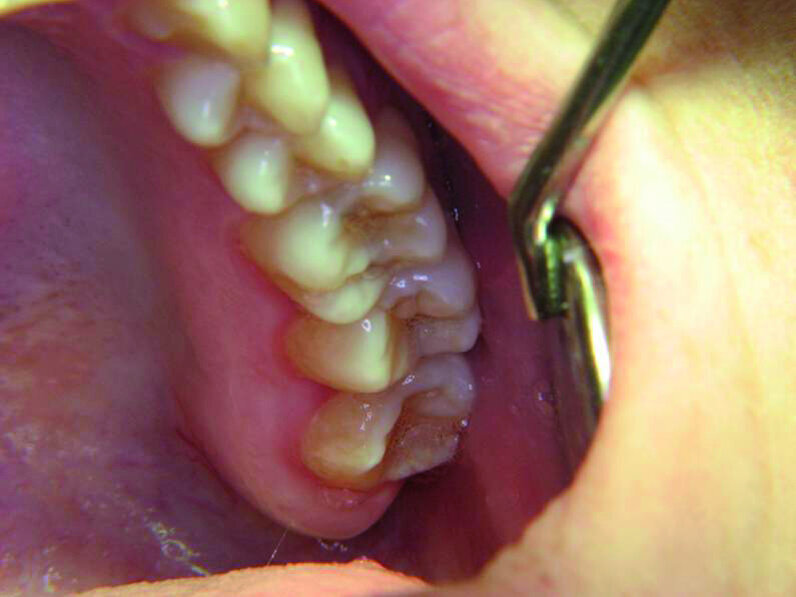

Les deuxièmes prémolaires peuvent être résumées par les mots « je veux créer » ou « mon moi créatif » (Fig. 3). La deuxième prémolaire supérieure droite symbolise ce que l’on veut développer dans le monde extérieur, nos enfants ou nos hobbies, et la deuxième prémolaire supérieure gauche nos dons naturels. La deuxième prémolaire inférieure droite, similairement à la première prémolaire adjacente, témoigne de notre capacité d’accomplir nos projets, particulièrement dans le domaine du travail. Ainsi, après la restauration d’une anodontie au moyen d’un bridge sur inlay, une jeune patiente dans l’indécision a terminé brillamment ses études au grand bonheur de ses parents (Fig. 4). Par contre les figures 5 et 6 sont des photographies de patients chez qui l’évolution professionnelle se place toujours au second rang des priorités.